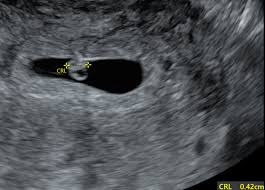

When we went back for our second ultrasound at 9 weeks and 3 days our baby is measuring at 8 weeks and 6 days.

Four days later Friday I came in and they are now measuring my baby as 7 to 10 days behind because he had very slow growth between the two ultrasounds. If you measure 30cm 12in or less at 32 weeks or your customised results are below your range your midwife may offer you an ultrasound scan to be on the safe side. 3 days later at 9 weeks exactly I scheduled an appointment with my RE to confirm the baby was still doing well. But we had a positive pregnancy test about 55 weeks before this exam which would supposedly be the first day of my last period if we were off on our dates. Baby was measuring in the 20th percentile at 32 weeks midwife said this was no issue because everything looked fine and I am pretty small myself. They asked me to return for another scan. I had a private early scan at 7 weeks and there was only the gestational sac measuring 2177mm and a yolk sac. They did an internal ultrasound and the tech said the fetus is too. Born at 38wks at 6lbs so not that small and healthy.